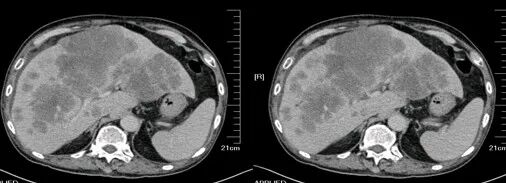

升结肠癌并广泛转移

气腹管怎么接肠梗阻、肠套叠、气腹、肝挫伤、脾挫伤、肾挫伤、胰腺损伤、食管癌、胃肠肿瘤_https://www.jmylbn.com_新闻资讯_第49张

气腹管怎么接肠梗阻、肠套叠、气腹、肝挫伤、脾挫伤、肾挫伤、胰腺损伤、食管癌、胃肠肿瘤_https://www.jmylbn.com_新闻资讯_第50张

升结肠癌

气腹管怎么接肠梗阻、肠套叠、气腹、肝挫伤、脾挫伤、肾挫伤、胰腺损伤、食管癌、胃肠肿瘤_https://www.jmylbn.com_新闻资讯_第51张

气腹管怎么接肠梗阻、肠套叠、气腹、肝挫伤、脾挫伤、肾挫伤、胰腺损伤、食管癌、胃肠肿瘤_https://www.jmylbn.com_新闻资讯_第52张

升结肠癌并肝转移